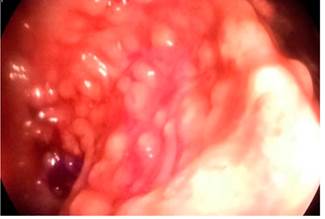

In addition, multiple 5-15 cm sessile, soft, ulcerated and hemorrhagic pseudopolypoid lesions located in the sigmoid colon and rectum were observed on videocolonoscopy (Figures 5 and 6).

Figure 6 Multiple 5-15 cm sessile, soft, ulcerated and hemorrhagic pseudopolypoid lesions on the mucosa of the sigmoid colon and rectum as observed on videocolonoscopy.